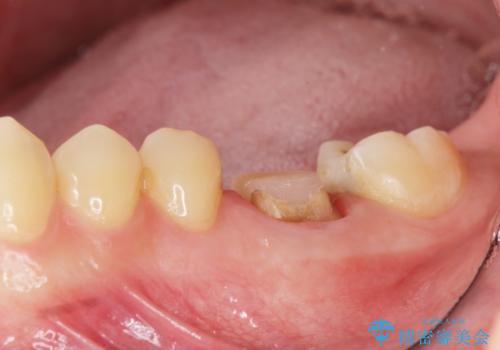

放置してしまった歯 根管治療からの機能回復

- 放置してしまった歯が痛み、いよいよ耐えられなくなり来院されました。

根管治療の途中で放置してしまっていた歯を、最終的に機能回復できるよう治療を行っていきます。

治療途中の歯の放置は、より虫歯を進行させてしまい抜歯に至ってしまうこともあるので注意が必要です。